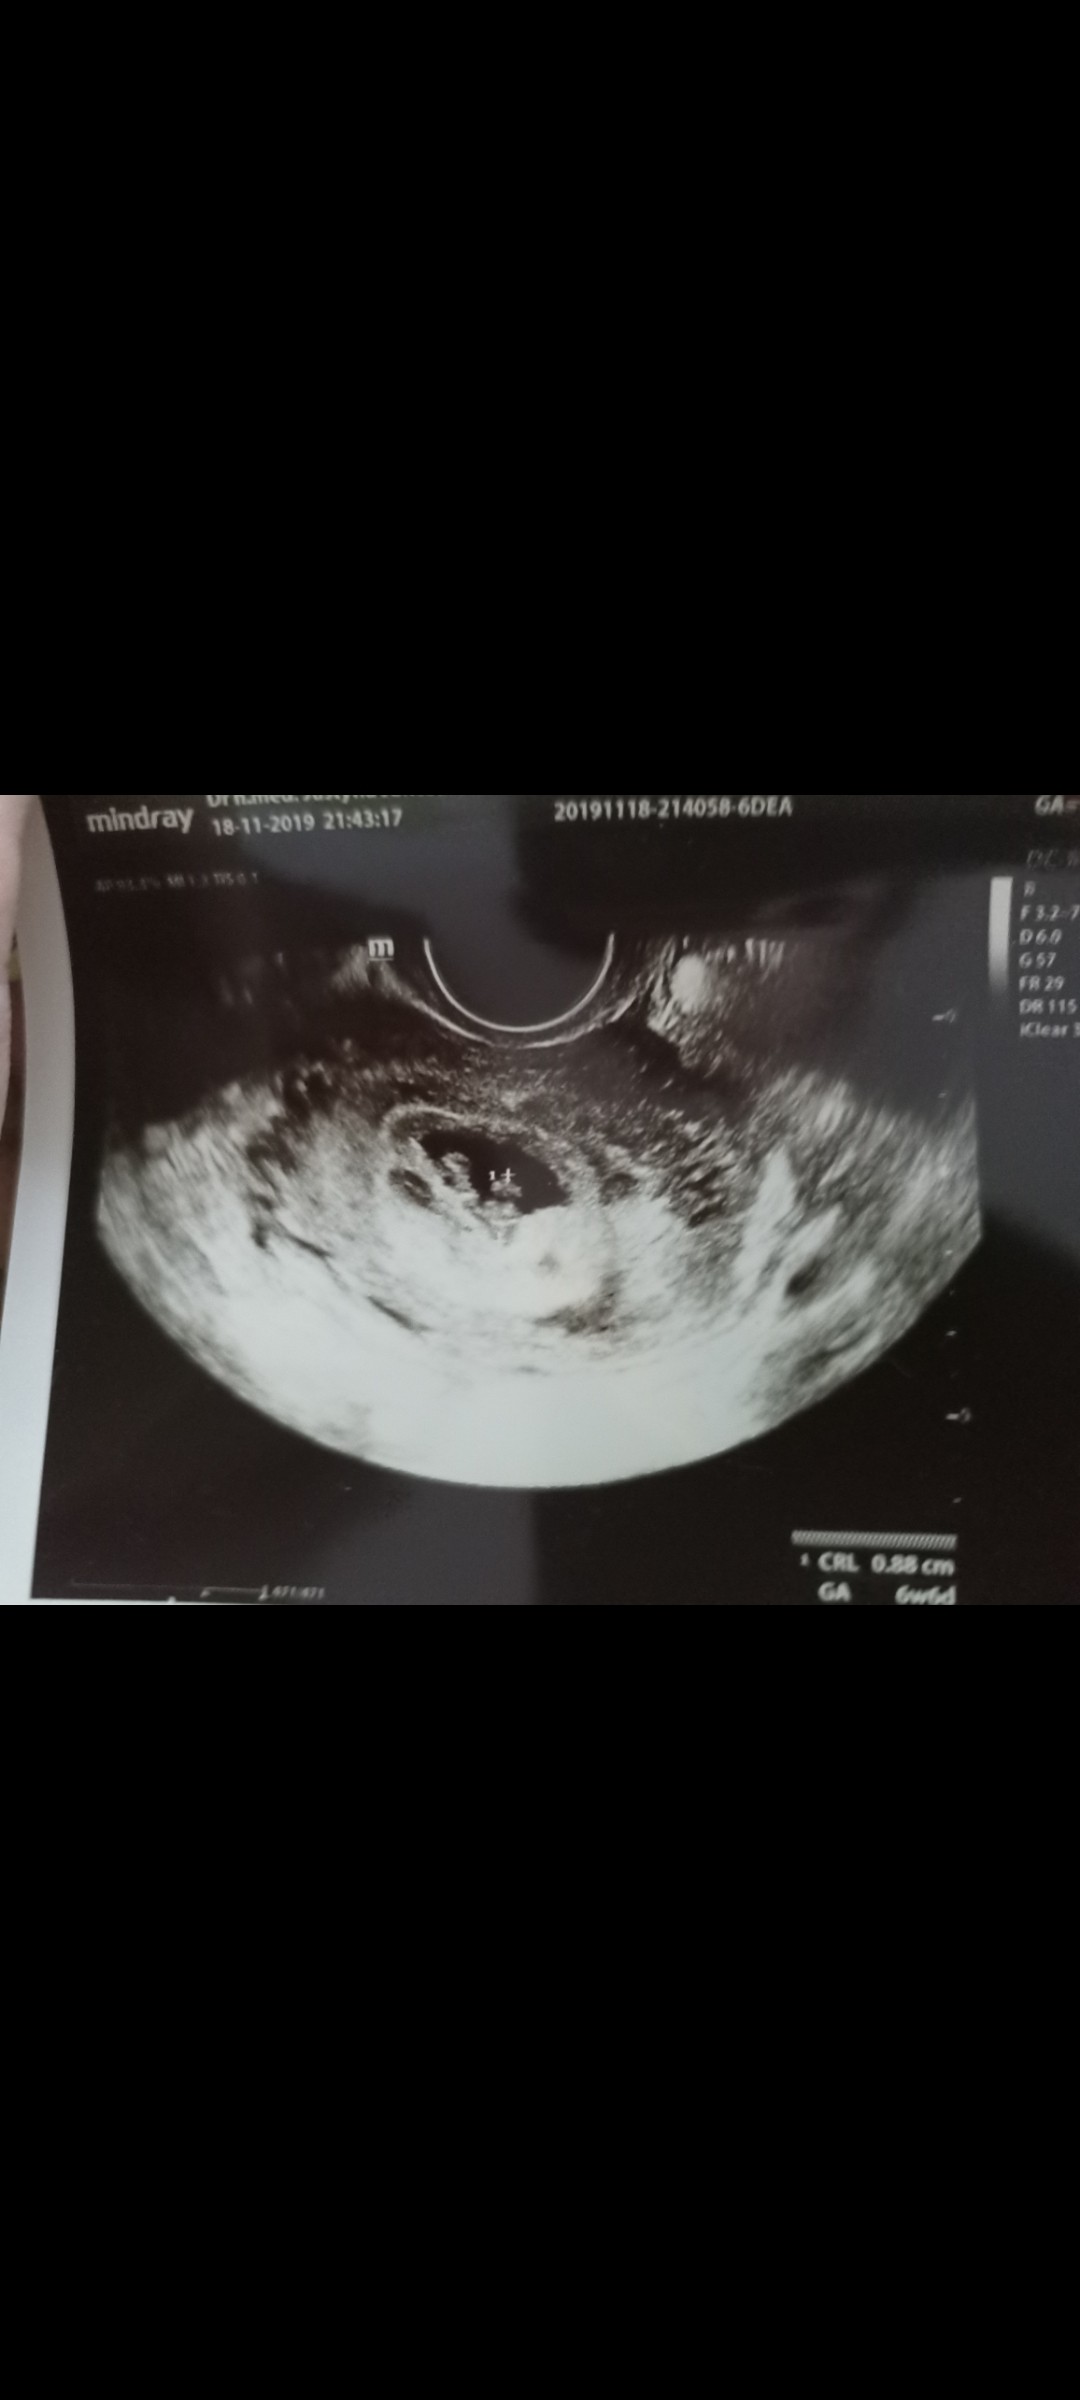

Ale generalnie lekarze się boją. I @EWELISIA 19 pada ofiarą tego strachu, że dajmy nadzieję. Do kiedy będą czekać? Tydzień temu był zarodek, teraz go nie ma.

Tylko dziwi mnie to że sama autorka nie zainteresowała się tym że wtedy był zarodek a teraz lekarz go nie widzi ,bo rzecz jasna ze przez tydz to chyba nawet z bardzo złym sprzętem lekarz by go zobaczył !I że jej samej nie daje to do myślenia?!Albo jest tak zaślepiona tymi swoimi lekarzami ,albo żyje w totalnie złudnych nadziejach i nie dopuszcza do siebie innej opcji . Może to wynika z młodziutkiego wieku autorki? Absolutnie nie chcę tutaj wieku uznawać za totalny brak wiedzy ale sam jej tok myślenia mówi sam za siebie .